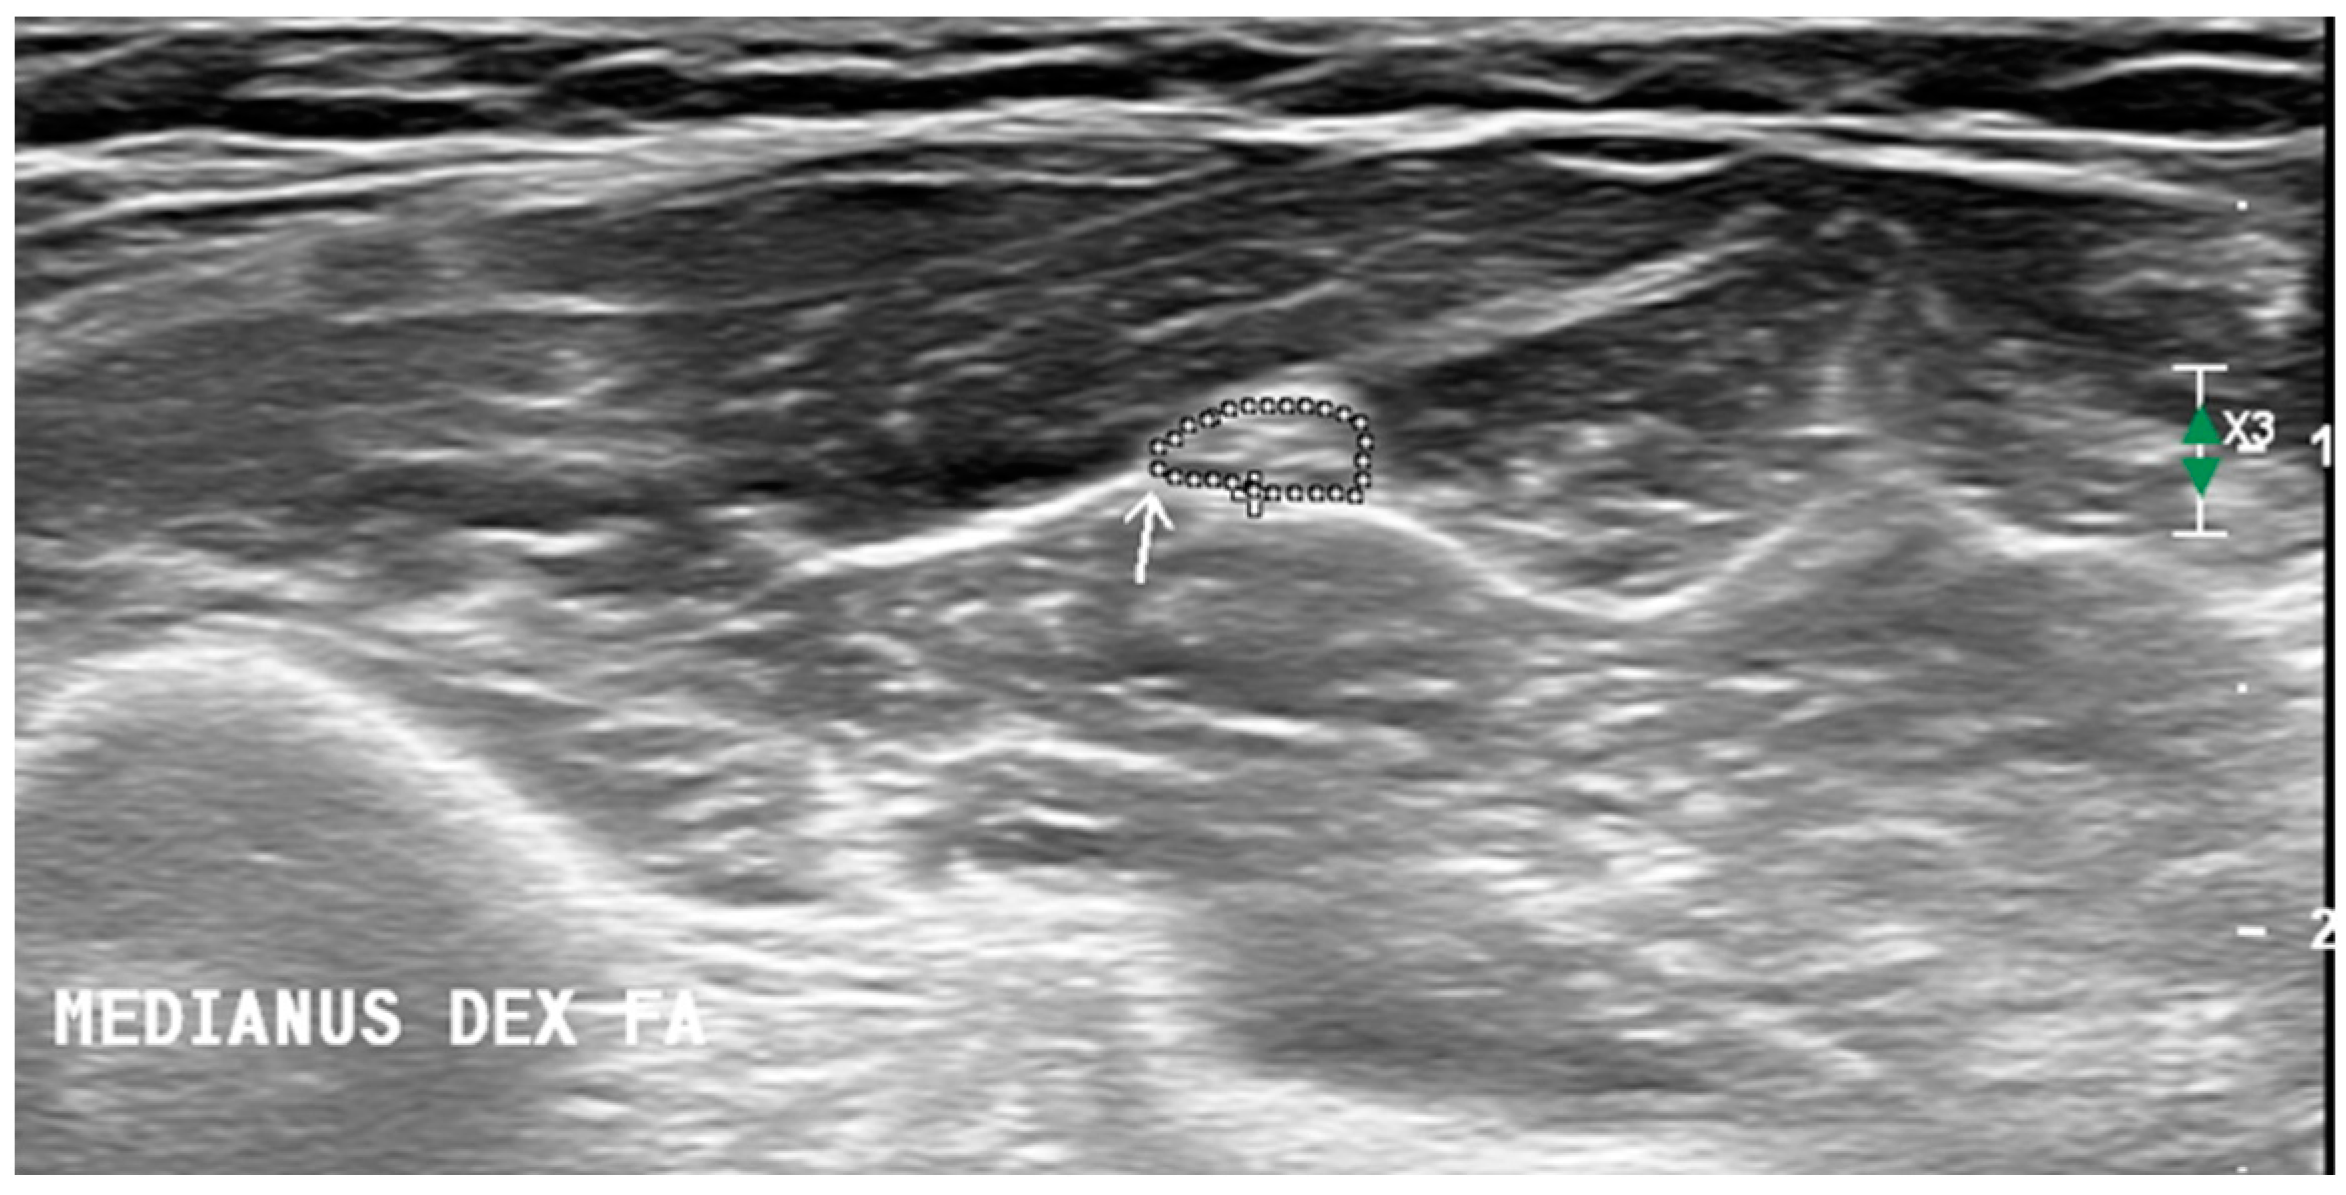

We performed an ultrasound of the peripheral nerves and brachial plexus bilaterally and chose which side to start the examination in a randomized manner. The upper (UT) and middle trunks (MT) of the brachial plexus were measured in interscalene space, and the fifth (C5) and the sixth (C6) cervical roots were measured in two ways: perpendicularly (at the point where roots appear between the anterior and posterior tubercle of the transverse process) and longitudinally (just after leaving the transverse process). The vagal nerve (VN) was measured at the level of the carotid triangle. Upper limb nerves: median (MN) and ulnar (UN) measurements were recorded at the middle of the upper arm, elbow, and the middle of the forearm (the MN was also measured at the wrist and UN at Guyon’s canal), the radial nerve (RN) was measured at the spiral groove, and superficial RN was recorded at the arcade of Frohse. Lower limb nerves: tibial nerve (TN) and fibular nerve (FN) were measured at the popliteal fossa, and TN was measured at the ankle beneath the vascular arcade the sural nerve (SN) was measured next to the saphenous vein at the lateral ankle and in the calf. These measurement sites were chosen based on the Neuropathy ultrasound protocol (NUP) [11] and Ultrasound Pattern Sum Score (UPSS) [12] protocols. The size of the brachial plexus (except longitudinal view) and peripheral nerves were assessed by measuring the cross-sectional area. The CSA of the nerve was calculated automatically by tracing the circumference of the nerve along the hyperechoic epineurium (Figure 1). A tracer tool was used for all the CSA measurements, except cervical roots and brachial plexus trunks were measured using the ellipse function. For longitudinal images of cervical roots, a diameter measurement was used, measuring the distance between one side of the epineurium to the other.

Figure 1.

Cross-sectional area measurement methodology. Arrow is pointing to the median nerve at the forearm. CSA of the nerve is circled along the hyperechoic epineurium.